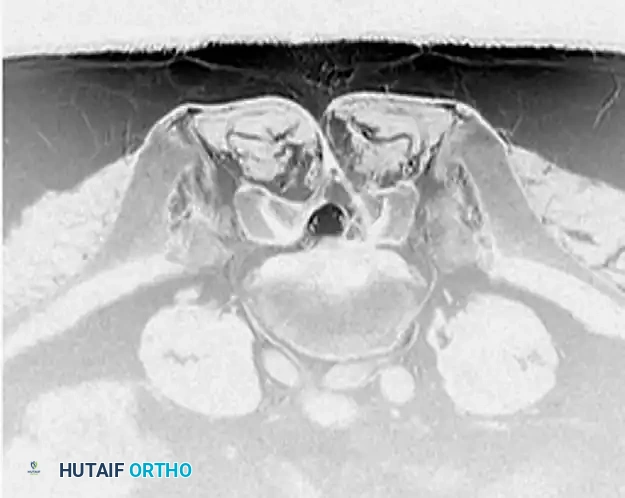

Diagnostic Imaging

Advanced neuroimaging is critical for preoperative planning. Magnetic Resonance Imaging (MRI) remains the gold standard, providing unparalleled visualization of neural elements, disc hydration, and the exact morphology of the herniation.

Image

Axial T2-weighted MRI sequences allow the surgeon to differentiate between central, paracentral, foraminal, and extraforaminal (far-lateral) herniations, which directly dictates the surgical approach.